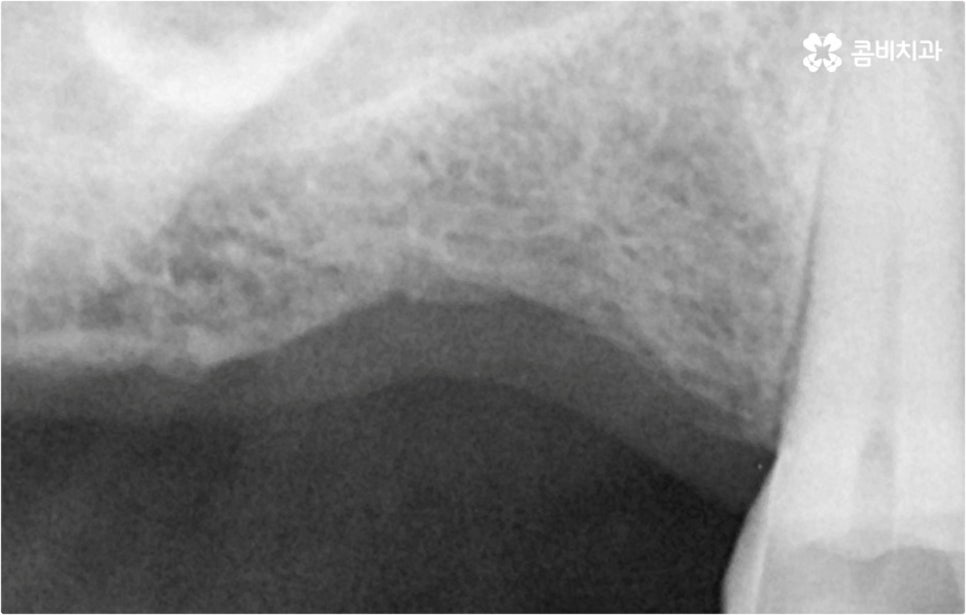

예를 들어 사고를 통해 한꺼번에 여러 개의 치아가 부러지거나 빠진 경우 연령 또는 전신 질환 여부 등을 살펴보고 치조골 상태가 양호하다면 보다 빠르고 간편한 당일 식립 방식을 이용해 볼 수 있어요. 그러나 하나 둘씩 치아가 빠질 때 마다 제때 치료를 해 주지 않아 치료 시기를 놓치고 결과적으로 무치악 상태에 이른지 오래 된 경우 또는 틀니를 오래 착용하여 잇몸뼈가 이미 많이 내려앉은 경우라면 바탕이 되는 잇몸뼈를 보충해 준 후 식립을 진행하는 방식을 이용해야 할 거예요.

또한 상악동과의 거리가 짧다면 거상술을 선행해야 할 수도 있고 심각한 치주 질환이 원인이라면 이를 먼저 깨끗하게 치료해 준 후 식립을 진행해야 성공률 또는 지속률이 높아질 수 있어요.

또한 이를 위해서 치아 주변 조직과의 거리나 잇몸뼈 높이, 밀도 등을 정확하게 파악할 수 있도록 도와주는 3D CT와 같은 정밀 진단 장비를 갖추고 환자분들의 상황에 맞는 계획을 세워 무리하지 않게 진행할 수 있는 체계적인 시스템을 운용하는 치과에서 임플란트 시술을 받으실 필요가 있어요. 만약 치과내 자체 기공소를 갖추고 있다면 보철물 제작에 대한 피드백이 보다 빠르게 전달, 반영될 수 있어 환자분들이 이용하시기에 좀 더 편안하실 거예요.